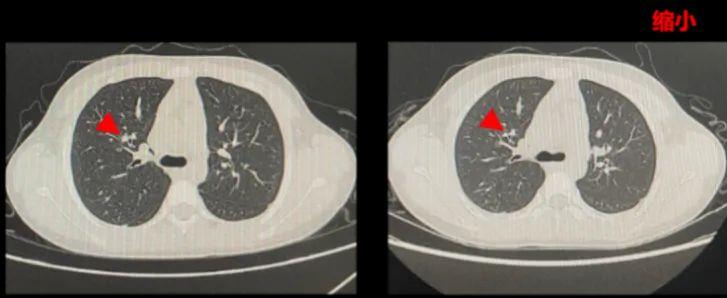

一位软组织恶性梭形细胞肿瘤伴肺部转移的患者,基因检测显示ETV6-NTRK3融合,接受化疗和9个周期的第一代TRK抑制剂后出现疾病进展。在国内接受5个周期ICP-723的治疗后,肺部非靶病灶明显缩小、右大腿靶病灶达到手术条件,右大腿病灶手术切除后病理提示已未见肿瘤组织。